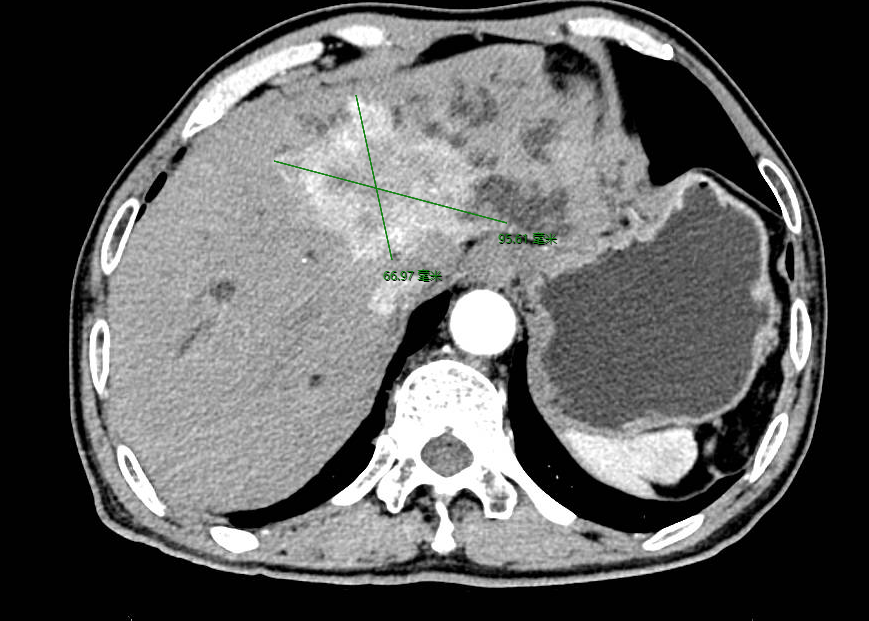

七旬患者王先生(化名)3个月前发现自己的尿液颜色异常发黄,严重时甚至黄得如浓茶水般。同时,他的上腹部也经常胀痛,并伴随反酸和烧心的感觉,这些症状似乎在暗示着某种严重疾病,让他非常焦虑。